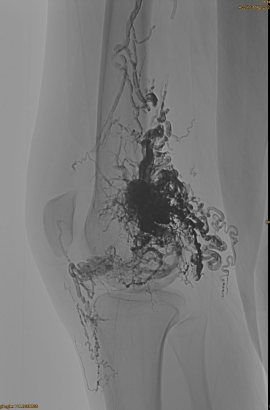

Основна інформація пацієнта: жінка, 36 років; AVM таз, стегно, коліно, ліва OSG, декілька попередніх засобів для -.

Використовувані продукти: 3pcs Lava-34,14pcs Lava-18.

Початковий DSA:

Кінцевий результат:

Навряд чи венозний відтік:

Пізня фаза, ще один ЕМБО, необхідний, але набагато краще: